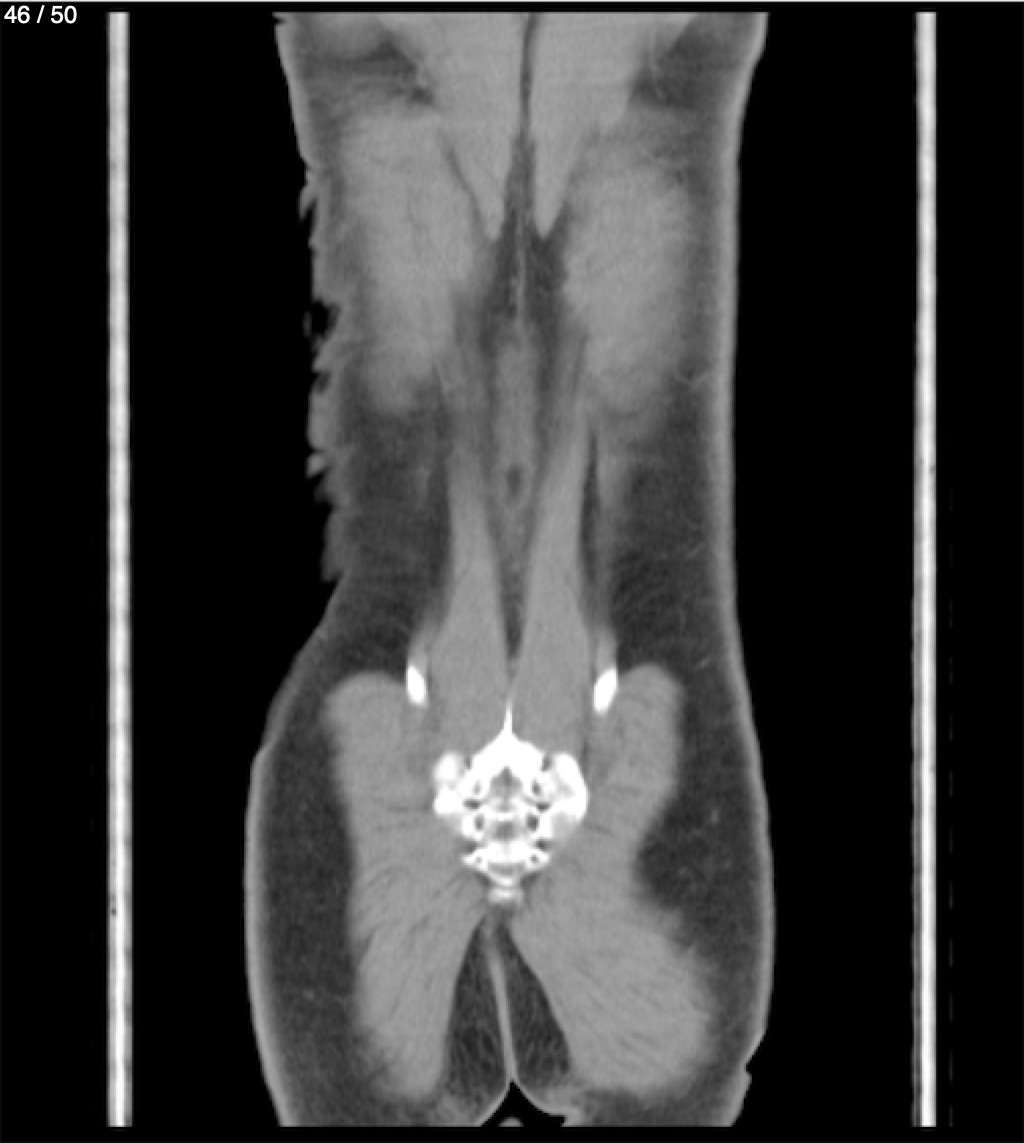

Alonso Victorio Ruiz 62A - T.C Abdomen Syc